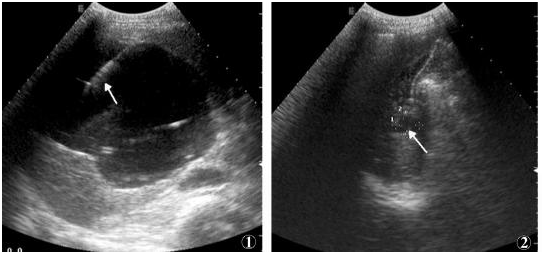

近日,我院綜合外科在同彩超室宋海霞主任的協(xié)作配合下共同完成一例在彩超引導(dǎo)下的肝囊腫穿刺、硬化術(shù)。手術(shù)患者為74歲女性,以頸痛伴眩暈入院,診斷為頸椎病,經(jīng)過對(duì)癥治療后患者病情好轉(zhuǎn),當(dāng)我科醫(yī)生在查看該患者的彩超檢查時(shí),卻意外地發(fā)現(xiàn)患者患有肝囊腫,并且符合穿刺、硬化治療的指征,在經(jīng)過與患者及家屬進(jìn)行有效的溝通后,手術(shù)于近日進(jìn)行。

超聲引導(dǎo)下肝囊腫硬化治療于70年代應(yīng)用于臨床,目前已經(jīng)成為肝囊腫的一種安全、有效的治療方法,具有全程可視、安全精準(zhǔn)、價(jià)格低廉、并發(fā)癥輕微、創(chuàng)傷小、恢復(fù)快等特點(diǎn),對(duì)肝囊腫的治愈率達(dá)90%以上。且對(duì)于復(fù)發(fā)的囊腫仍然可以再次進(jìn)行治療,因此在臨床上應(yīng)用越來(lái)越廣泛,如腎囊腫、多囊肝、多囊腎、卵巢囊腫、腘窩囊腫等。